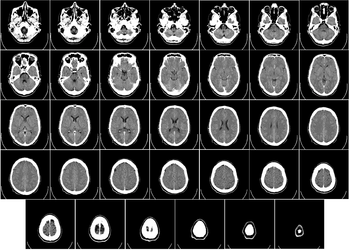

Head

CT scanning of the head is typically used to detect infarction, tumors, calcifications, haemorrhage and bone trauma. Of the above, hypodense (dark) structures can indicate edema and infarction, hyperdense (bright) structures indicate calcifications and haemorrhage and bone trauma can be seen as disjunction in bone windows. Tumors can be detected by the swelling and anatomical distortion they cause, or by surrounding edema. Ambulances equipped with small bore multi-sliced CT scanners respond to cases involving stroke or head trauma. CT scanning of the head is also used in CT-guided stereotactic surgery and radiosurgery for treatment of intracranial tumors, arteriovenous malformations and other surgically treatable conditions using a device known as the N-localizer.[12][13][14][15][16][17]